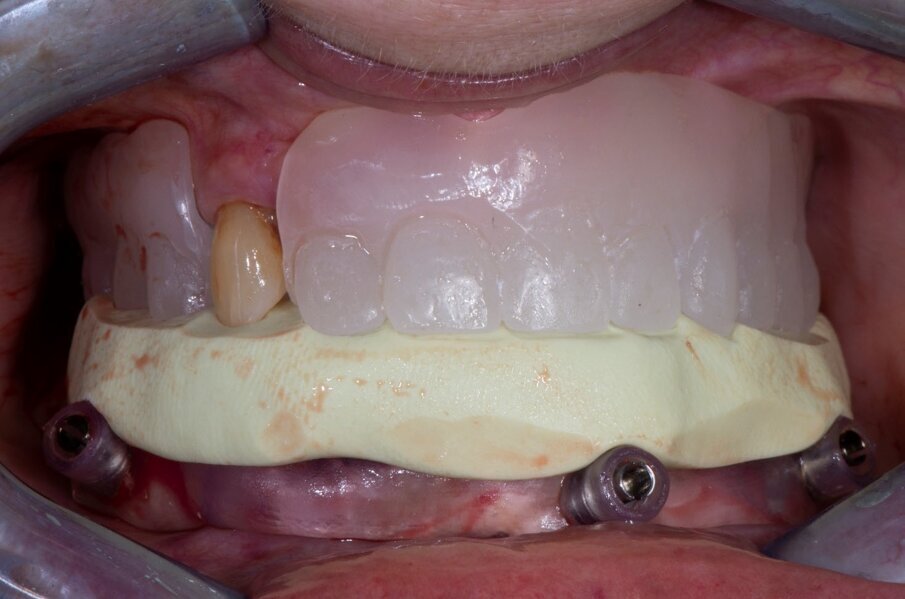

Fig. 10_Risultato finale.

Da qui in poi inizia la fase protesica con l’avvitamento dei MUA e subito sopra di essi, l’avvitamento delle torrette che ospiteranno la protesi che viene fissata con del cemento dual. Questo passaggio permetterà di rendere la struttura provvisoria passiva.